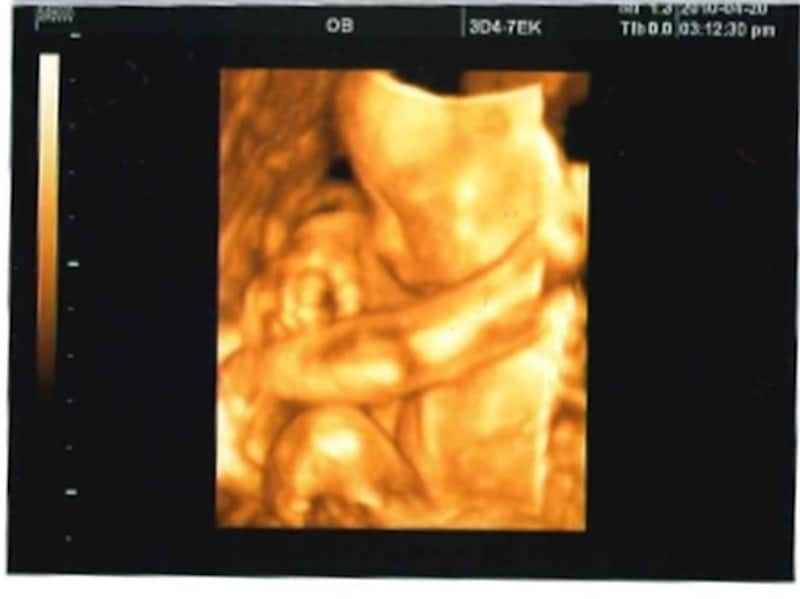

妊娠23週(23w)の赤ちゃんは、安定したぺースで成長中。特に変化が著しいのが体重ですが、この増加のほとんどは、筋肉や骨、内臓組織の発達によるものです。膵臓(すいぞう)も発達していきます。皮膚はかなりシワシワですが、これから皮下脂肪が少しずつ増えて、筋肉も発達してくると皮膚の表面はなめらかになっていきます。

聴覚が発達中で、赤ちゃんはお腹の中で、色々な音を聞いています。いちばん聴いている音はお母さんの心音、肺を空気が満たす音、息を吐く音、お腹や腸がなる音、そして、お母さんの声。聴覚が完成するのは妊娠26週くらい、生まれて間もない赤ちゃんは、すでにお母さんとの声を聞き分けられるといいます。たくさん話しかけてみましょう。